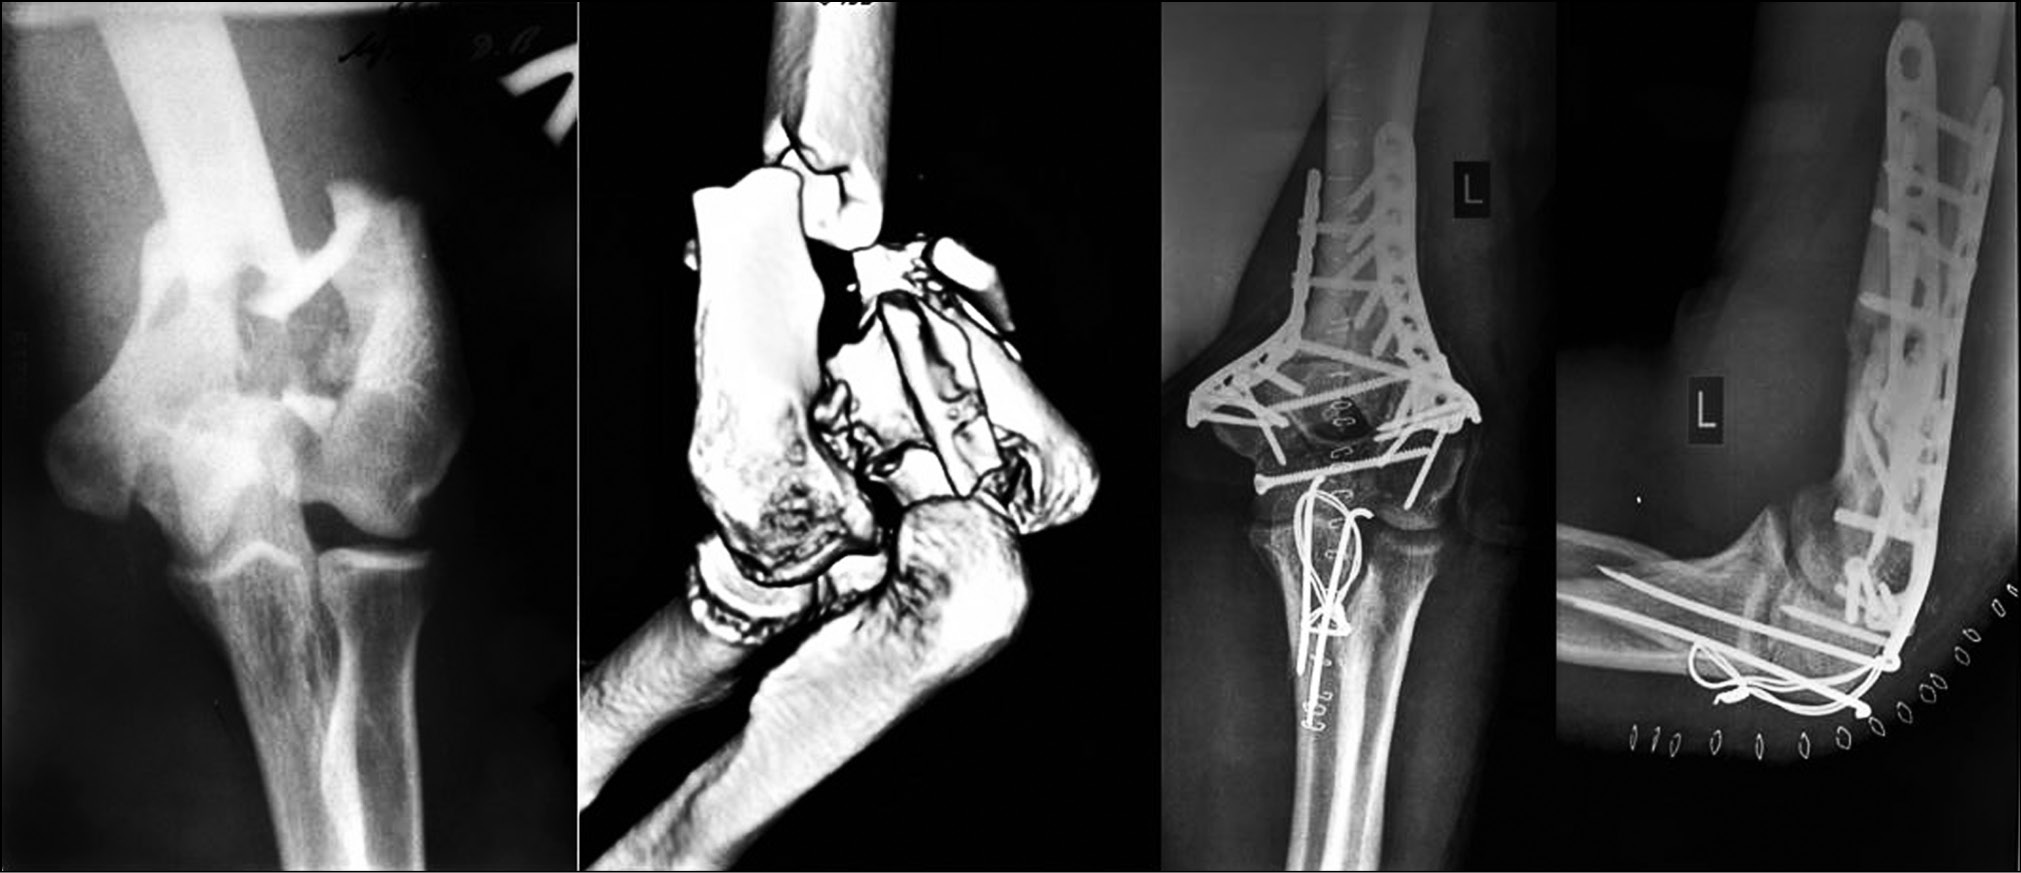

Для остеосинтеза выполняли разрез кожи по задней поверхности локтевого сустава длиной 15–20 см с последующим доступом к локтевому отростку с мобилизацией и транспозицией локтевого нерва. Все последующие этапы выполняли под контролем электронно-оптического преобразователя. Для доступа к внутрисуставному перелому дистального метаэпифиза плечевой кости осуществляли клиновидную остеотомию локтевого отростка с мобилизацией и отведением сухожилия трехглавой мышцы плеча. У 12 пациентов использовали доступ без остеотомии локтевого отростка. Далее производили репозицию костных отломков с восстановлением конгруэнтности суставной поверхности и фиксацию 2-мя пластинами по наружной и внутренней боковым или наружной боковой и задней медиальной поверхностям мыщелка плечевой кости (рис. 1). При изолированных переломах блока выполняли репозицию отломков и проводили направляющие спицы перпендикулярно линиям перелома. По направляющим спицам рассверливали каналы и выполняли фиксацию перелома введением в каналы канюлированных компрессионных винтов, выполненных из титанового сплава или сополимера молочной кислоты (polylactic-co-glycolic acid — PLGA), с погружением головки винта до субхондральной пластинки, обеспечивая полное внутрикостное расположение фиксатора (рис. 2). Затем выполняли остеосинтез предварительно остеотомированного локтевого отростка проволокой и спицами по Веберу. Операционную рану ушивали послойно, формируя при этом ложе для локтевого нерва. Следующим этапом на локтевой сустав накладывали заранее скомпонованный ШДА Оганесяна, который фиксировали задней штангой с умеренной дистракцией в локтевом суставе в среднефизиологическом положении. Активную разработку движений в суставе в условиях шарнирно-дистракционного аппарата с постепенным увеличением амплитуды начинали с 2-х суток с момента операции.

Рис. 1. Остеосинтез перелома мыщелка плечевой кости пластинами

Fig. 1. Osteosynthesis of the fracture of the condyle of the humerus with plates

Рис. 2. Остеосинтез перелома мыщелка плечевой кости канюлированными винтами

Fig. 2. Osteosynthesis of the fracture of the condyle of the humerus with cannulated screws